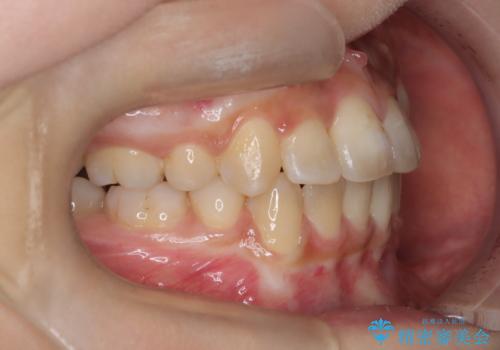

重度の歯並びの乱れを改善|上下4本抜歯と審美ワイヤー矯正で美しい歯列へ

- 患者様は、歯並びのガタガタ(重度の叢生)を改善したいとのことで来院されました。診察すると、歯列のスペース不足が著しく、前歯が重なり合い、噛み合わせにも影響が出ている状態でした。歯をきれいに並べるためには抜歯によるスペース確保が不可欠と判断し、上下の小臼歯4本を抜歯したうえで、目立ちにくい審美ワイヤー矯正(白いワイヤーと透明ブラケット)を用いた治療計画を立てました。

抜歯によって歯を動かすためのスペースを確保。その後、審美ワイヤー矯正を用いて歯を1本ずつ適切な位置に誘導しながら、噛み合わせのバランスも整えていきました。時間はかかりましたが、ガタガタの歯並びがきれいに整い、機能的にも審美的にも満足のいく仕上がりとなりました。患者様からは「歯並びが劇的に改善し、見た目だけでなく噛みやすさも向上した」と喜びの声をいただきました。